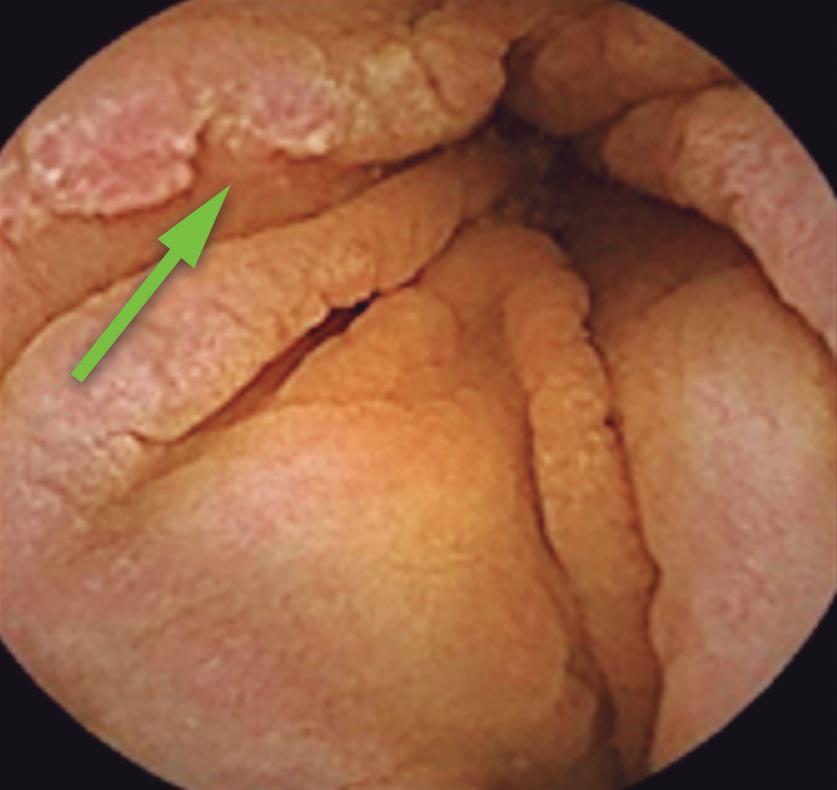

Otra lesión tumoral no dolorosa la constituye la presencia de verrugas genitales (condilomas) producidas por el VPH (virus del papiloma humano). Pueden ser pequeñas o grandes y confluyentes, con un aspecto coliforme de coloración blanquecina. (Figura 2) En estos pacientes es conveniente la investigación de otras enfermedades de transmisión sexual. El estudio con anoscopia de alta resolución facilita la detección de lesiones de alto grado preneoplásicas.4 (Figura 3) El tratamiento de las lesiones del VPH es esencial para prevenir el contagio, la extensión de las lesiones por autoinoculación y la progresión a neoplasias. En este artículo se describen tratamientos tópicos, ablativos y resectivos, como por ejemplo topicación con ácido tricloroacético, imiquimod, electrofulguración, láser o resección quirúrgica.4

Figura 2. Condilomas perianales de superficie coliforme blanquecinos, típicos de lesión por VPH de bajo grado

Figura 3. Anoscopia de alta resolución 20X. Lesión condilomatosa endoanal de bajo grado sobre la línea pectínea (flecha)